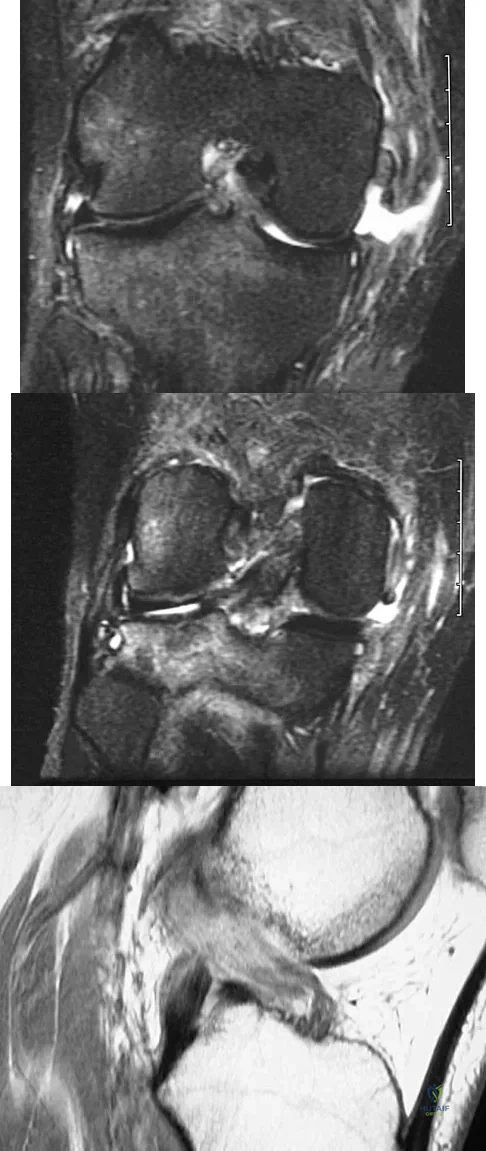

Figure 11 shows a consecutive sequence of MRI scans obtained in a 12-year-old boy who has had increasing lateral knee pain and catching for the past 6 months. Examination reveals pain localized to the lateral joint line. Range-of-motion testing reveals a 5-degree lack of full extension on the involved side. Plain radiographs and laboratory values are within normal limits. What is the most appropriate management?

Discoid menisci are rare causes of lateral knee pain in children. Various etiologies have been proposed, including failure of central absorption of the developing meniscus and hereditary transmission. Patients with discoid menisci have pain, clicking, and locking with a loss of active extension on range-of-motion testing. Classification of discoid menisci according to the Watanabe classification include complete, incomplete, and Wrisberg ligament type. The Wrisberg variant contains an abnormal posterior meniscal attachment. MRI is the diagnostic tool of choice, revealing a thick, flat meniscus generally seen in three consecutive MRI images. Symptomatic knees are often associated with a meniscal tear or degeneration and are managed with arthroscopic partial excision to a more normal shape (saucerization). Vandermeer RD, Cunningham FK: Arthroscopic treatment of the discoid lateral meniscus: Results of long-term follow-up. Arthroscopy 1989;5:101-109.